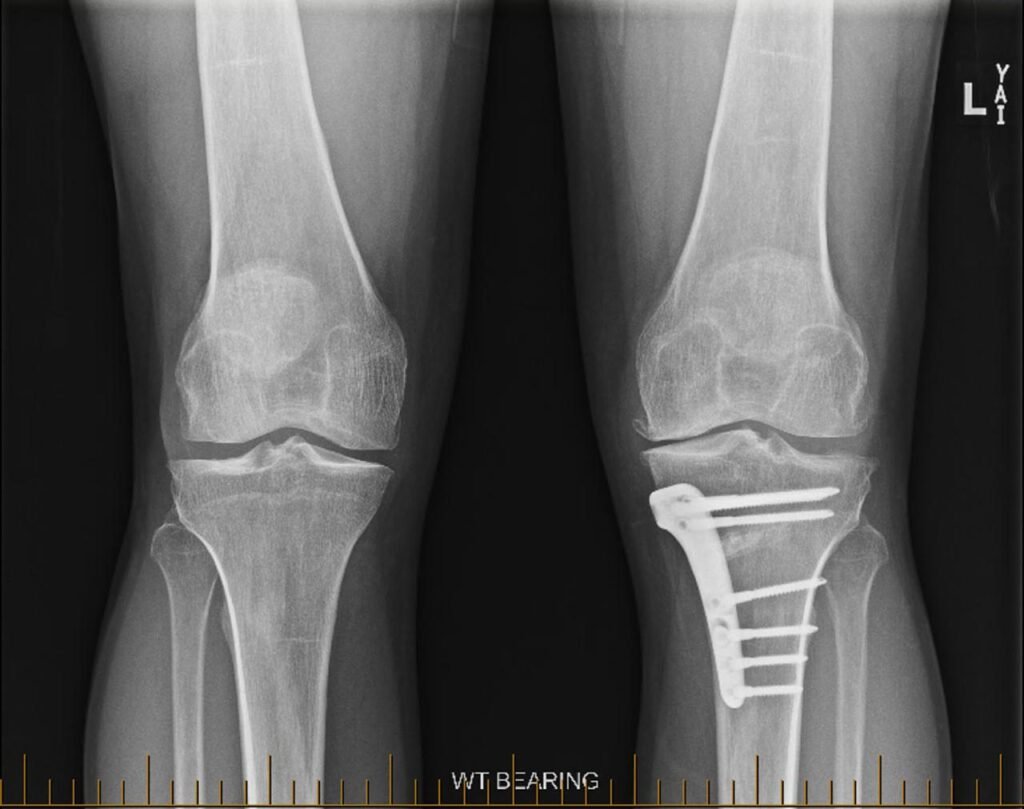

High Tibial Osteotomy (HTO)

A high tibial osteotomy involves cutting and reshaping the upper part of the tibia (shinbone). It is most commonly used in patients with varus deformity, where the knees are bowed outward and excess pressure is placed on the inner (medial) compartment of the knee. HTO works by shifting the body’s weight toward the less affected outer (lateral) part of the knee joint, aiming to reduce pain, improve function, and delay the progression of medial compartment osteoarthritis. This is the most common type of osteotomy performed for knee joint preservation.

4. The Surgical Procedure

- A small cut is made to access the tibia or femur, depending on the planned correction.

- A carefully measured wedge of bone is either removed (closing wedge) or created (opening wedge).

- The bone is realigned to redistribute load away from the worn part of the knee.

- The new alignment is secured with a specialised plate and screws.

- Bone graft or synthetic material may be used to support healing if needed.